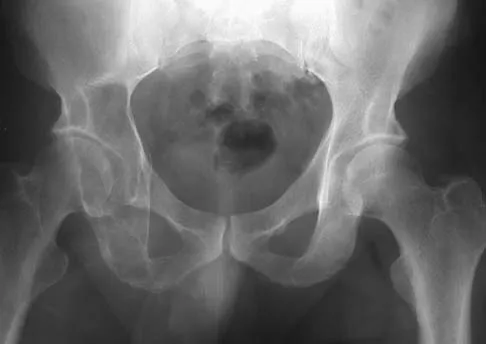

Question 48 High Yield

A 12-year-old boy reports the acute onset of pain and a pop over the right side of his pelvis while swinging a baseball bat during a Little League game. Radiographs reveal an avulsion of the anterior superior iliac spine with 2 cm of displacement. Management should consist of

Detailed Explanation